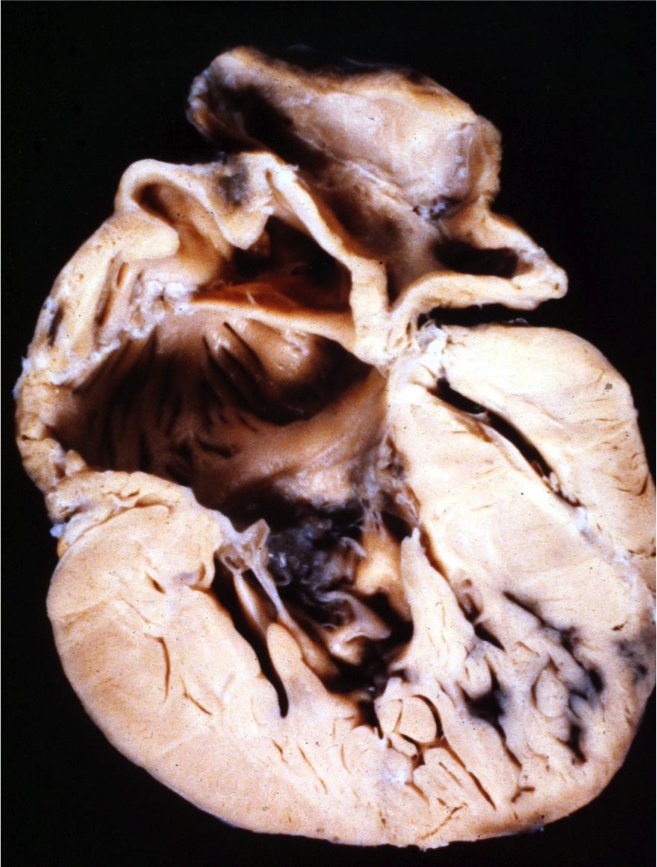

Nous consacrerons une séance aux obstacles sous aortiques de nature variable et évolutifs avec le temps, ce qui reste dans le thème.

Il y a ceux qui sont là, ceux qui apparaissent, ceux que l’on crée et puis la question lancinante de savoir ceux qu’il faut ôter sans savoir précisément quand ou comment.